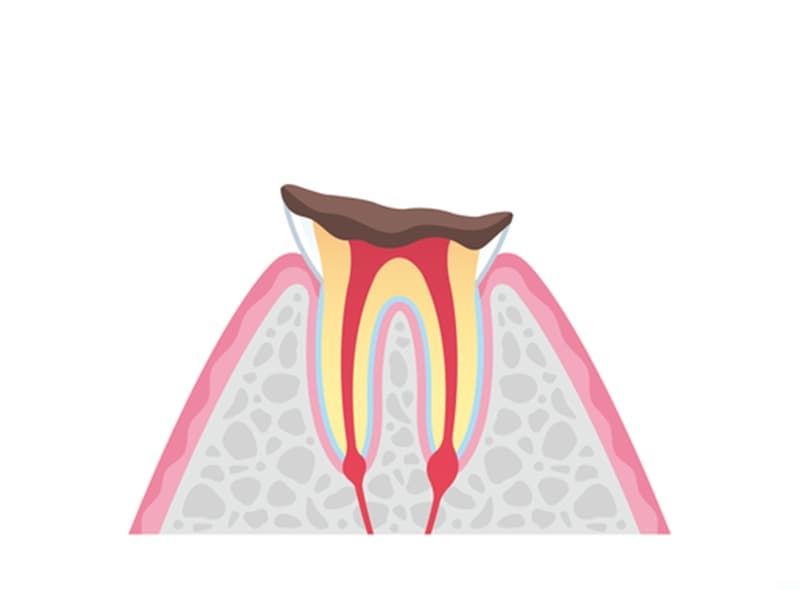

- C3

神経まで侵されたむし歯

むし歯が歯髄まで到達すると、激しい痛みを伴うのが特徴です。この段階では、感染した歯髄を除去し、根管治療を行う必要があります。根管内の感染組織を徹底的に除去・洗浄した後、特殊な材料で根管を封鎖。適切な修復物を装着して治療は完了します。